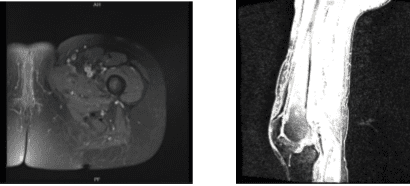

An MRI was reviewed and discussed by the doctor; Left Thigh MRI, the Bones T1 marrow signal intensity is maintained within without evidence for aggressive osseous lesion or osteonecrosis. No acute fracture is present. There is no marrow or periosseous edema.

Please note that this study was not tailored to evaluate for internal derangement of the Joints. Nevertheless, no significant joint effusions are present. There is an oblique tear in the posterior horn of the medial meniscus. The Muscles/Tendons has no full-thickness tendon tear or tenosynovitis is appreciated.

There is no disproportionate muscle atrophy. No acute muscle tear or denervation-related edema is present. There is no peri muscular fluid. The neurovascular structures demonstrate normal course.

The subcutaneous tissues are within normal limits. Oblique tear in the posterior horn of the medial meniscus. No fractures. No muscle tear or muscle edema in the thigh.

In left hip MRI, Bone and Joint there is severe joint space narrowing the left hip joint with bone-on-bone contact. There is subchondral bone marrow edema subchondral cyst in the lateral acetabulum and lateral aspect of the femoral head with bone marrow edema extending into the femoral neck and intertrochanteric fossa.

There is flattening of the femoral head. There is extensive full-thickness cartilage loss. There is a moderate left hip joint effusion with synovitis. There is diffuse tearing of the labrum. The Tendons/Muscles have visualized tensor fascia lata, rectus femoris, hamstring tendons and iliopsoas intact.

MRI Left thigh non-contrast

MRI Left hip non-contrast